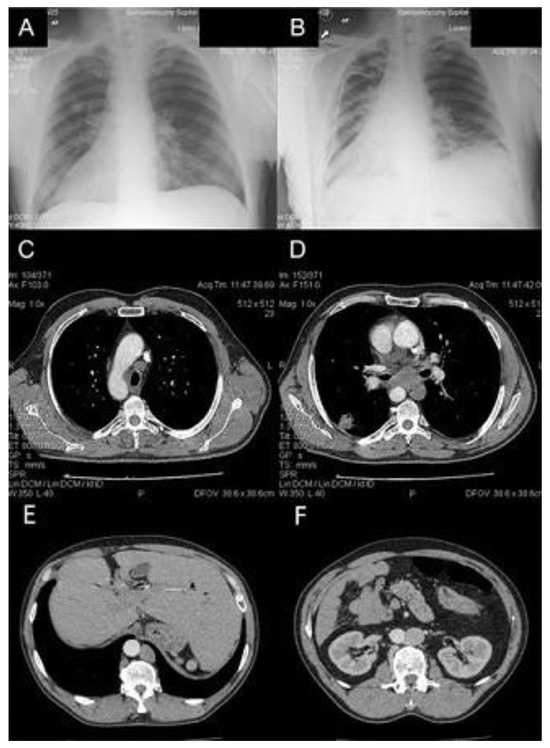

A 56-year-old man with previously confirmed SIT was admitted to the Thoracic Surgery and Transplantation Department in January 2014 due to a 2.5 cm tumor of unknown etiology in the right lung, detected in a chest X-ray. The patient did not present any clinical symptoms. The image of SIT was confirmed in a contrast-enhanced chest computed tomography (CT). In addition, CT confirmed a 28 × 22 mm tumor in the sixth right segment, with a 9 mm satellite tumor located slightly higher, with enlargement of the mediastinal lymph nodes (Figure 1). Positron emission tomography FDG-PET/CT and endobronchial ultrasound (EBUS) were inaccessible during hospitalization. The diagnosis procedure was extended with an ultrasound fine needle aspiration biopsy of the right lung tumor and left supraclavicular lymph node with a diameter of 6 mm. Lung tumor biopsy was ineffective and cancer cells were not observed in the supraclavicular lymph node biopsy specimen, although the high level of carcinoembryonic antigen CEA (95.3 ng/mL) suggested adenocarcinoma in stage N2. A bronchofiberoscopy showed the right side of the lobar opening segmental bronchi anatomy in a configuration typical of the left lung, and an analogous image on the left side, where the bronchial configuration of the lobar openings’ segmental bronchi anatomy corresponded to the right lung. Subsequently, the patient qualified for surgery via right thoracotomy. Intraoperatively, the correct anatomy of the left lung (bilobar lung) on the right side and the tumor in the sixth segment, corresponding to the chest CT, was found; however, the posterior part of interlobar fissure was undeveloped. The entire anatomy of the mediastinum also corresponded to the left side, including the nodal station of the aorto-pulmonary window. Intraoperative examination confirmed metastases to the nodes of groups 5 and 7 and the procedure was limited to the sixth segmentectomy with mediastinal and lung hilar lymphadenectomy. The surgical technique was based on reconstructing the posterior part of the interlobar fissure by scissor stapling and ligation of the artery and vein to segment VI, followed by the linear stapler resection of segment VI.

Figure 1. (A,B) Pre- and postoperative chest X-rays of the patient with SIT and lung cancer. (C,D) Chest CT showing rearrangement of mediastinal vessels and 2.5 cm tumor in VI right segment with enlargement of lymph nodes 4R and 7. (E,F) Abdominal CT showing position of the liver on the left side and position of the aorta on the right side.